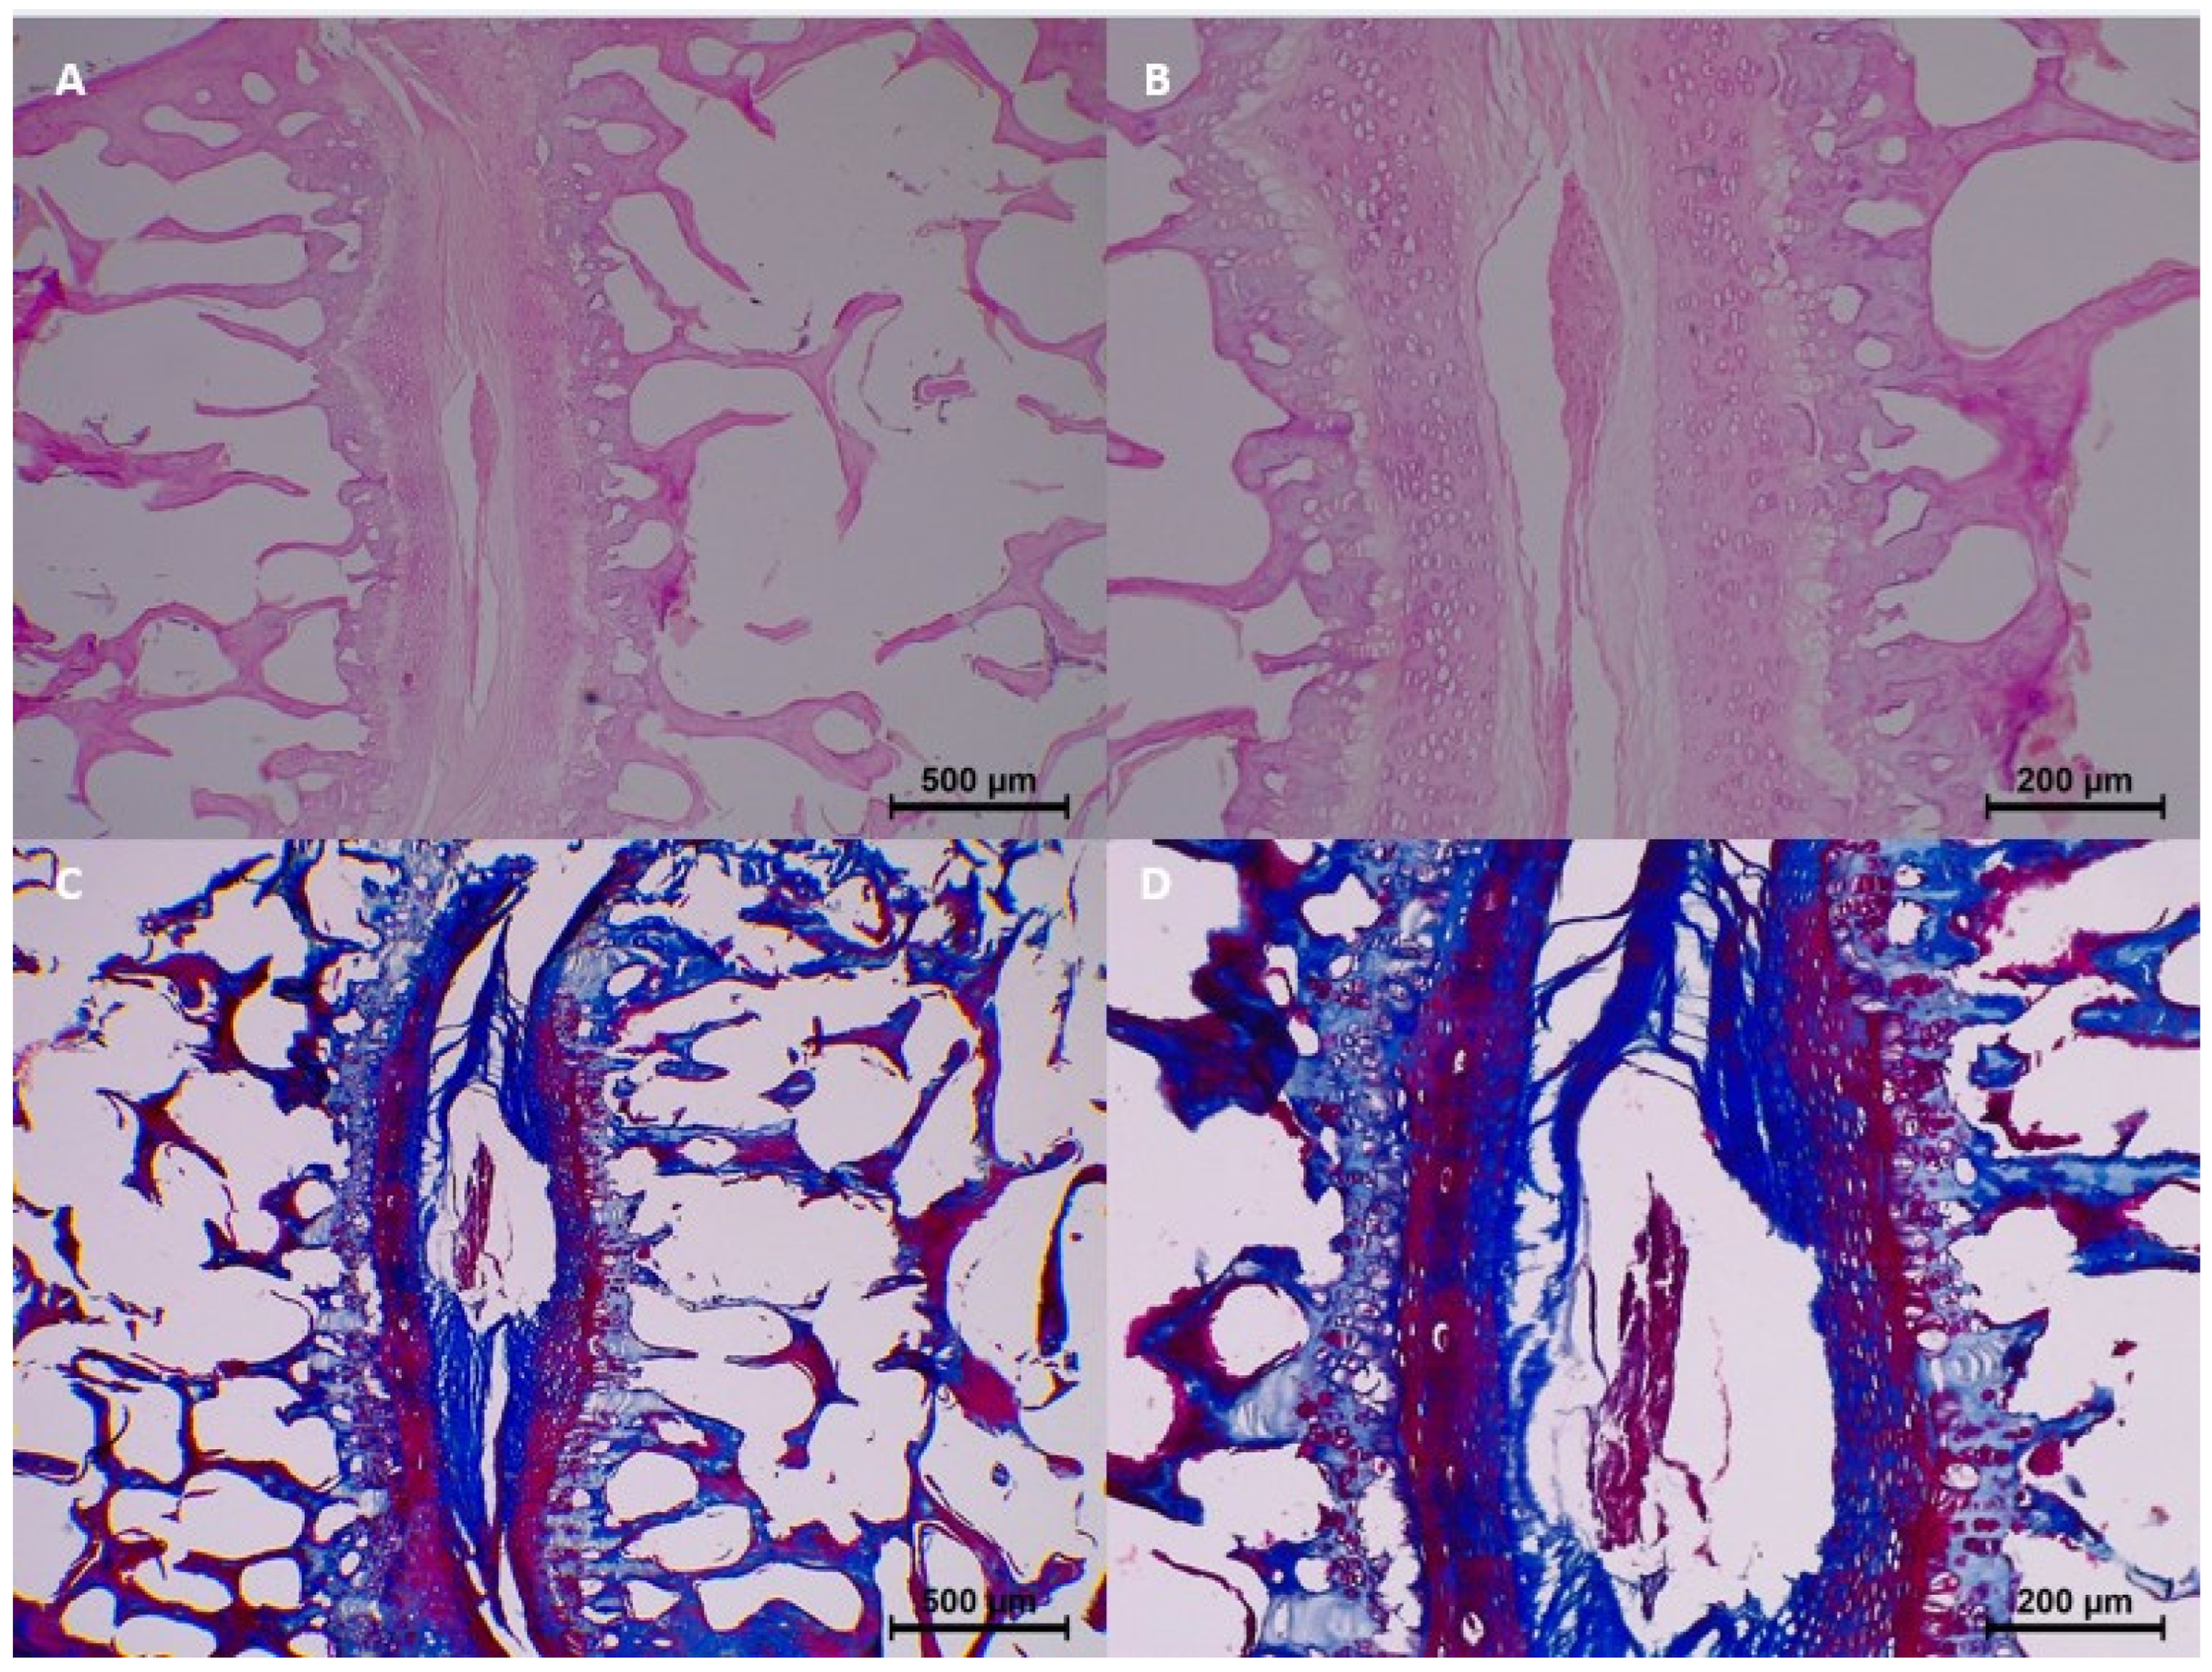

In the control group (0 h), no significant histopathological changes were observed. Homogenization, eosinophilia, dissociation, degeneration, pyknosis, and karyolysis were all absent, and collagen structure appeared normal (

Table 3 and

Figure 2).